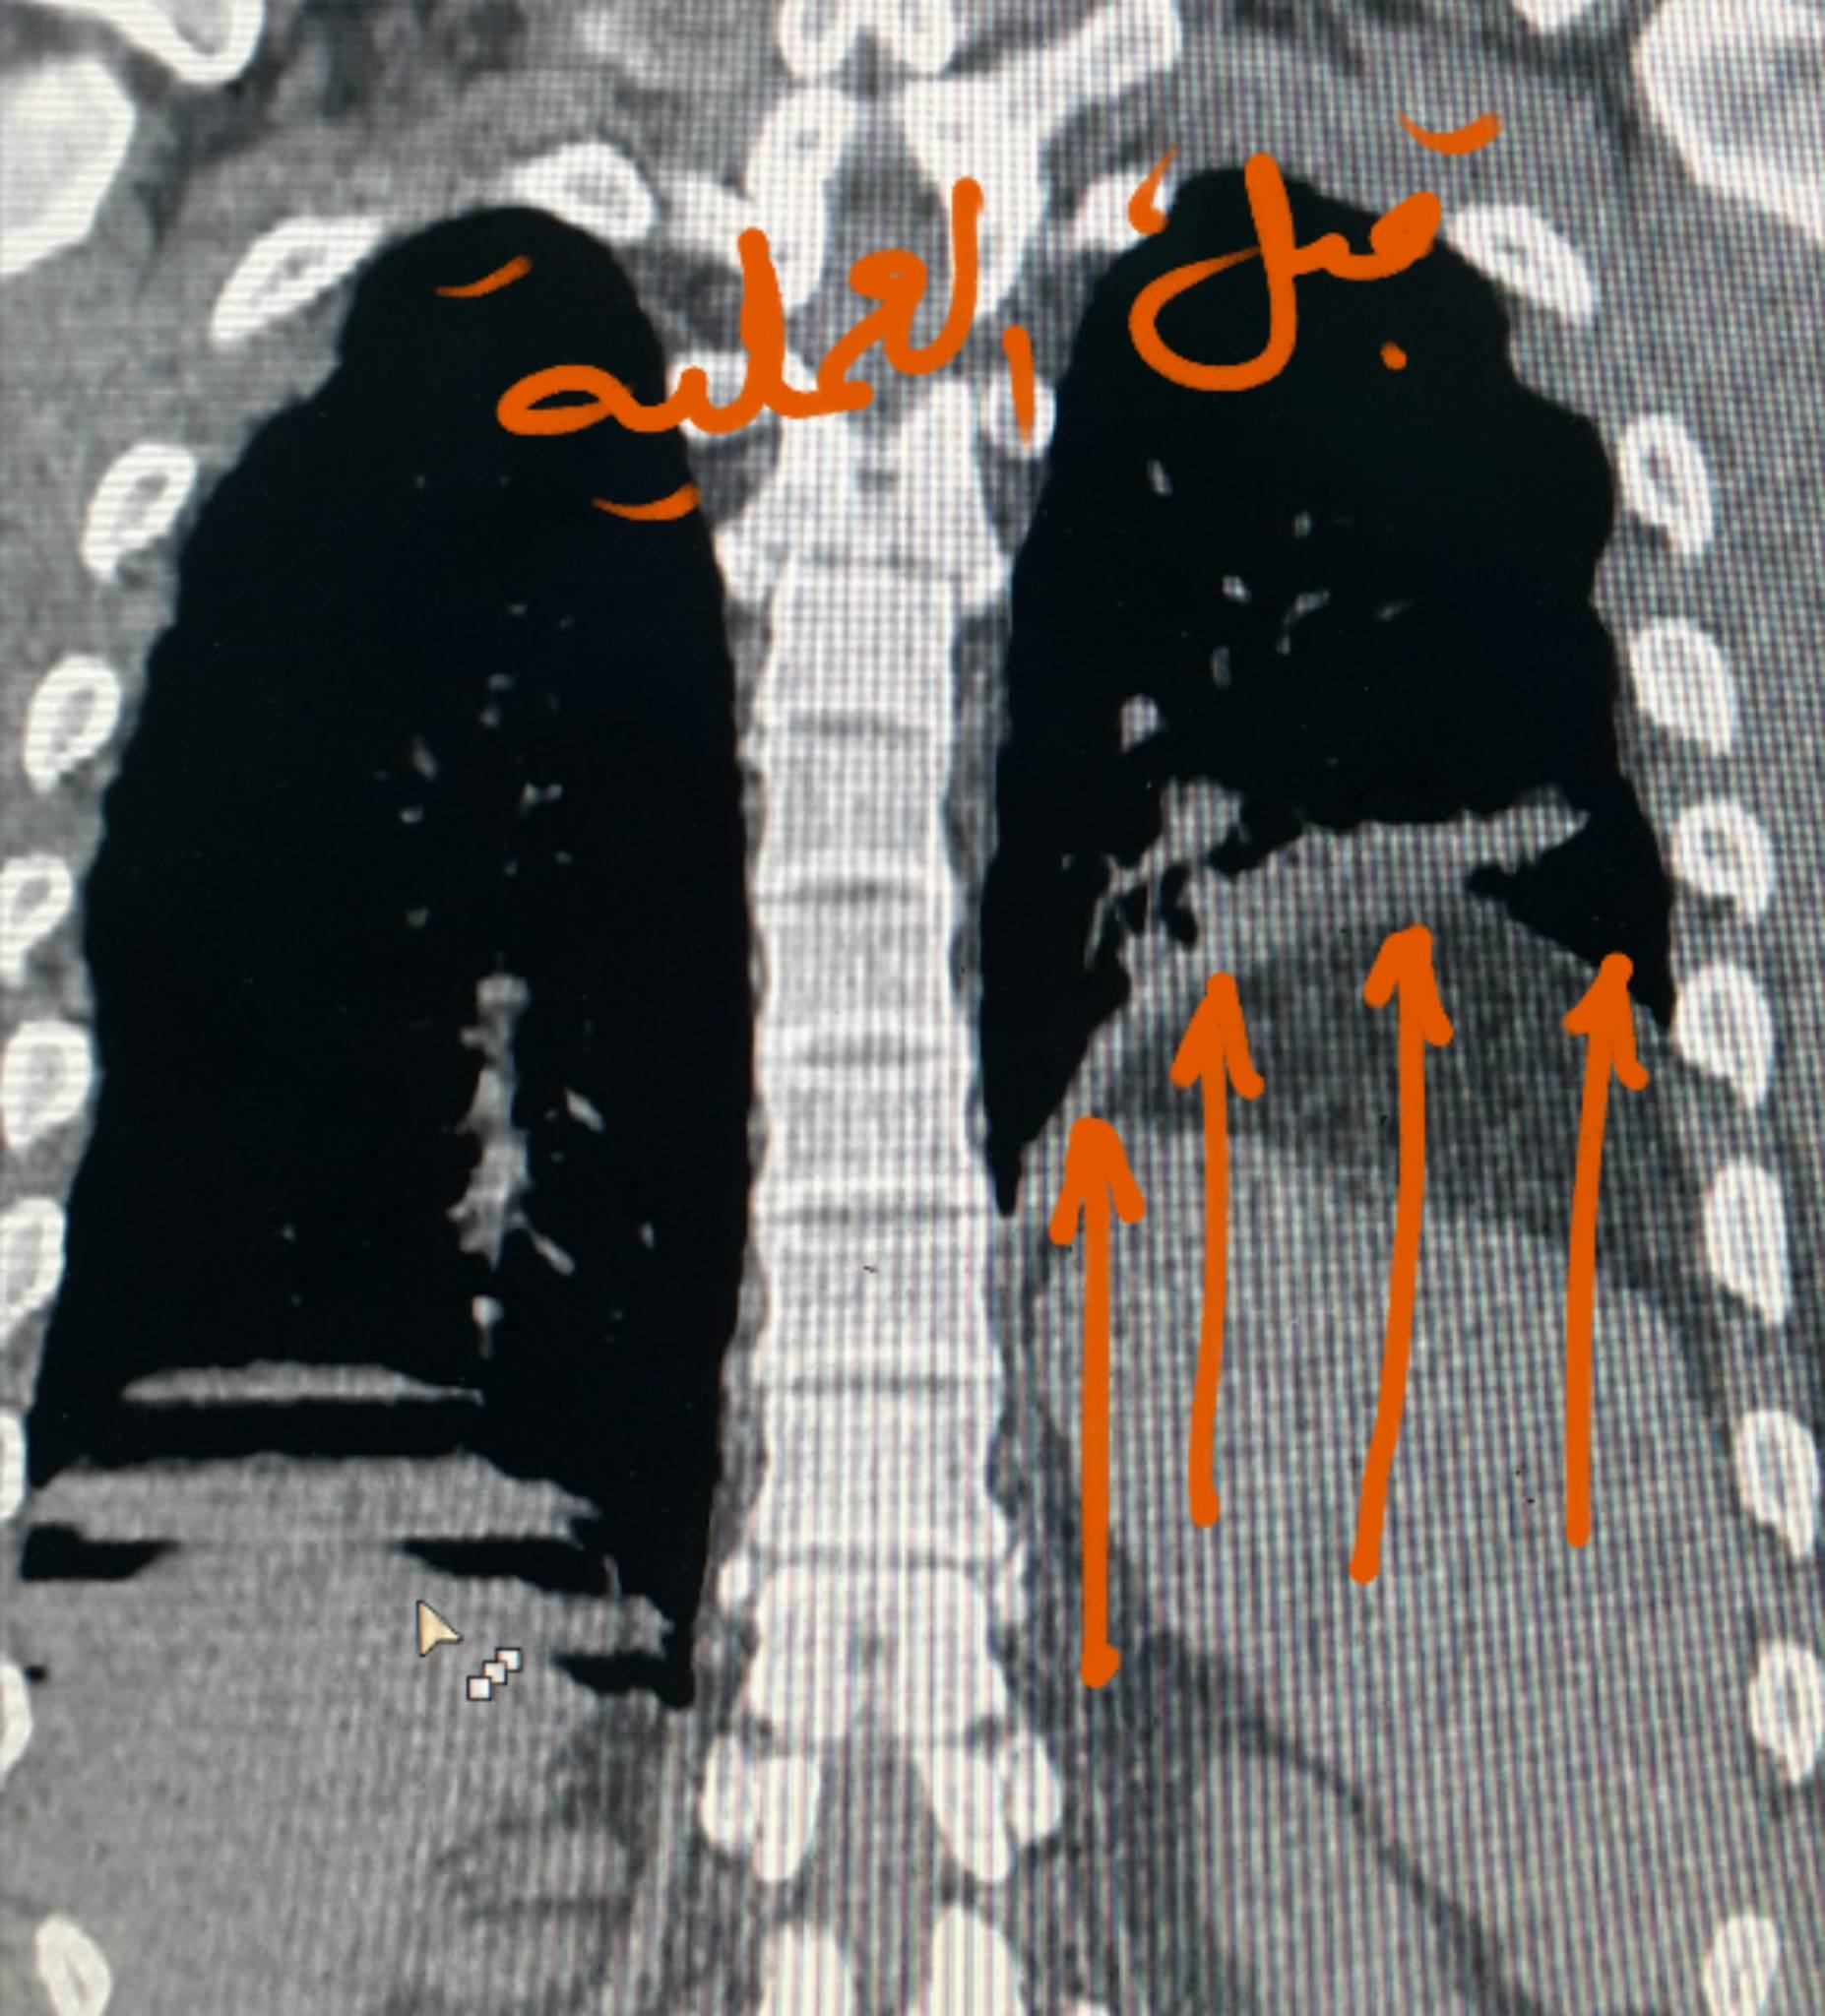

بالصور: إجراء عملية جراحية نوعية بمستشفى الخدمة العامة

غزة - فلسطين الآن

من جديد نجح الفريق الطبي بمستشفى الخدمة العامة برئاسة د. رائد العريني استشاري مناظير وجراحة الصدر والتشوهات الخلقية الصدرية والروبوت الجراحي وزراعة الرئة. و مساعده د.طارق شراب أخصائي الجراحة العامة وفريق العمليات بالمستشفى من إجراء عملية نوعية جديدة للمريض ز .ح البالغ من العمر 25 عام والذي يعاني من ضيق في التنفس منذ سنوات .

وأوضح د رائد العريني أن المريض يعاني منذ سنوات من ضيف في التنفس وحضر إلى المستشفى وقد أجري له الفحص الطبي الإكلينيكي والصور الإشعاعية والمقطعية حيث تبين وجود ارتخاء شديد لعضلة الحجاب الحاجز الأيسر مما يتسبب بصعود الحجاب الحاجز وأحشاء البطن من معدة وقولون والطحال إلى تجويف الصدر مانعا لتمدد الرئة اليسرى وصعوبة في التنفس.

والجدير ذكره أن د. العريني أجرى خلال الشهر الجاري عملية لمريض آخر يعاني من نفس المشكلة حيث لاقت نجاحا باهرا بحيث تحسنت حالة المريض بشكل كبير بعد إجراء العملية.

وأكد العريني أن المريض غادر المستشفى بصحة جيدة بعد مكوثه 3 أيام نقاهة، شاكرا الجهود المبذولة.